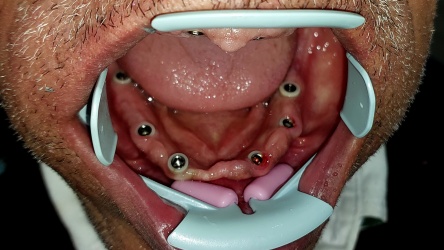

لاحظوا كيف انا اللثة زهريه حول كل زرعه بسبب العنق الزركوني الأبيض الذي يحيط بالزرعه والذي يحميها من التهابات اللثه وتراجع العظم وبالتالي تعيش عمر اطول بكثير من الزراعات العاديه لان سبب تراجع العظم و اهتزاز زرعات بعد عمر هو التهابات اللثه

تركيب الدعامات او الابوتمنت فوق الزرعات في كلا الفكين والتي ستلصق عليهم التركيبات النهائيه